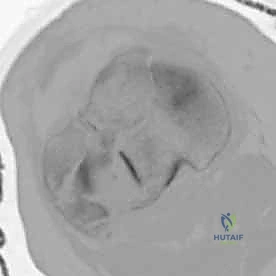

2. التصوير الإشعاعي (X-rays)

الخطوة الأولى هي التقاط صور أشعة سينية من عدة زوايا (أمامية خلفية، وجانبية). تعطي الأشعة السينية فكرة عامة عن وجود الكسر وموقعه، لكنها غير كافية لتقييم الكسور ثنائية اللقمة المعقدة.

3. الأشعة المقطعية المحوسبة (CT Scan) - المعيار الذهبي

لا يمكن إجراء جراحة لكسر ثنائي اللقمة دون إجراء أشعة مقطعية (يفضل مع إعادة بناء ثلاثية الأبعاد 3D).

* توفر الأشعة المقطعية خريطة دقيقة لكل شظية عظمية.

* تحدد مقدار الانخساف في السطح المفصلي بالمليمتر.

* تكشف الشظايا المخفية، خاصة في الجزء الخلفي من الركبة (Posterior Coronally oriented fragments) والتي تتطلب خطة جراحية خاصة لتثبيتها.